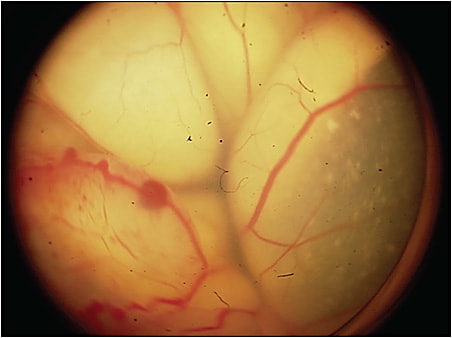

Unlike almost all human cancers, retinoblastoma is diagnosed without biopsy. Inadvertent entry into the eye of a child with retinoblastoma can be catastrophic; in a recent series, more than half of such patients developed metastatic disease and died.3 The differential diagnosis is extensive, with more than 30 intraocular lesions that simulate retinoblastoma. Some recent series show an error rate of 20% in some centers. Because of this, we have looked at a series of more than 30 typical retinoblastoma-simulating lesions, most common is Coats disease (Figure 2), and in all cases there was no RB1 cfDNA detected.4 A negative result does not mean the eye does not have retinoblastoma, as previously mentioned, but a positive result indicates that the lesion is not a simulating one.